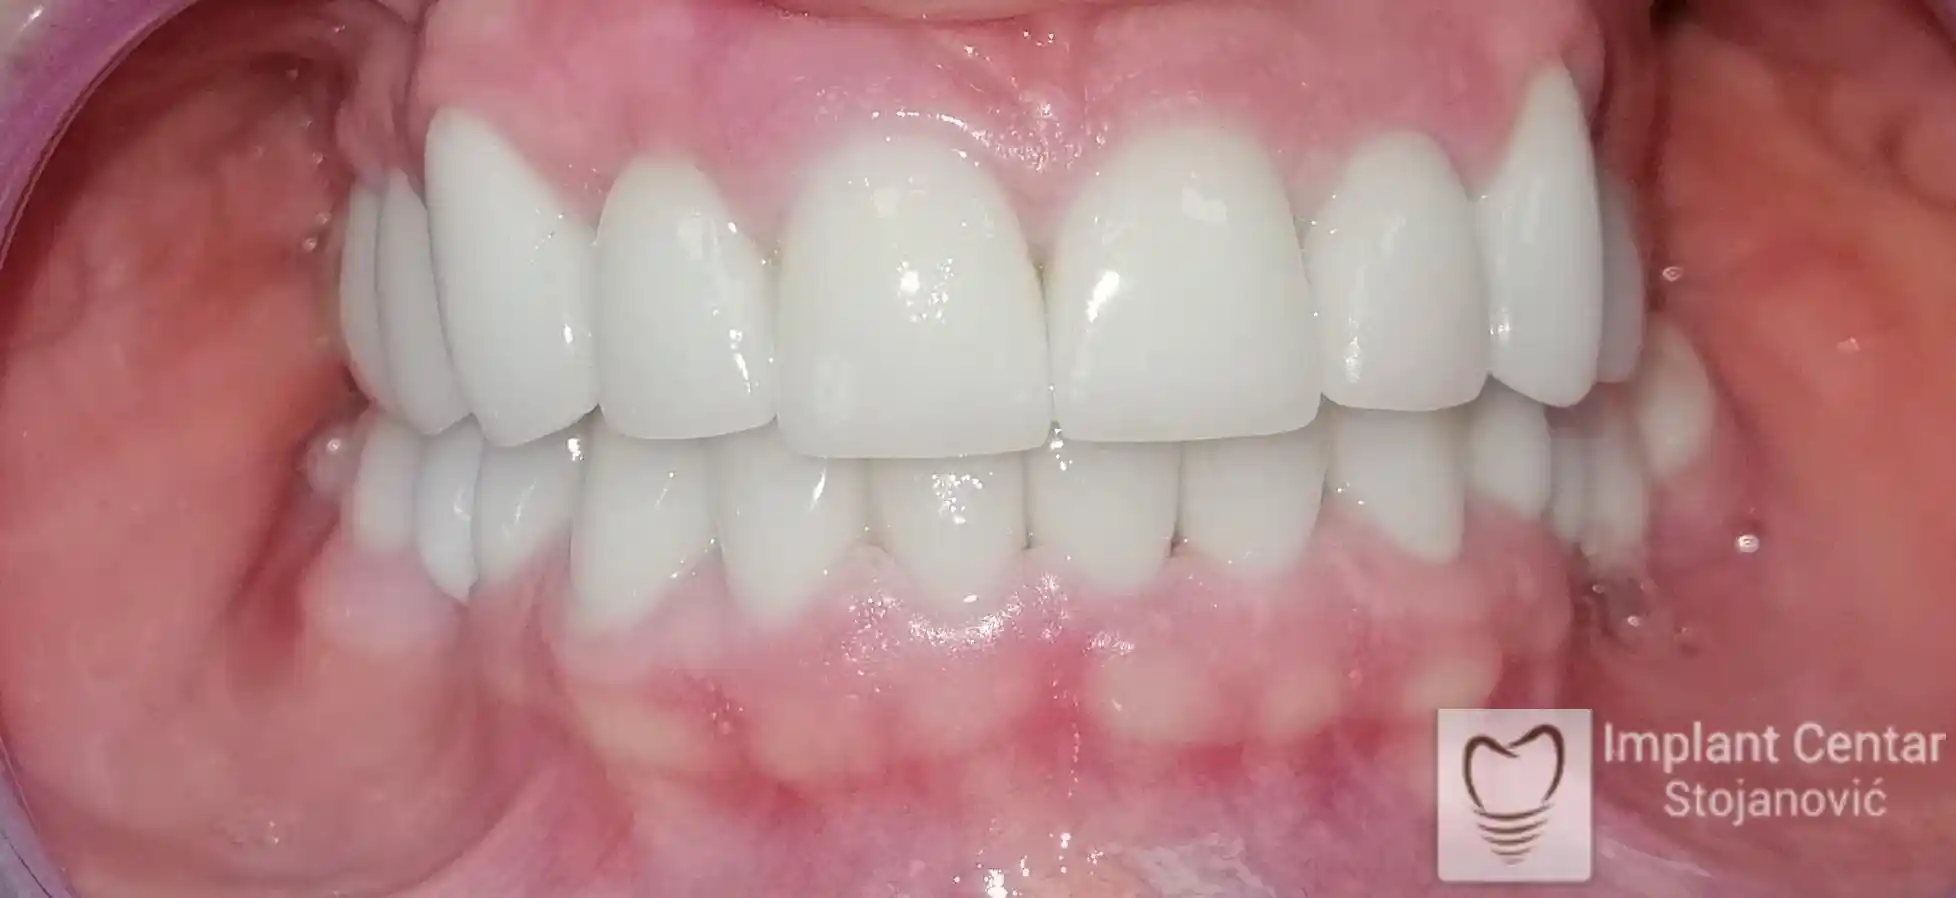

Tokom perioda oseointegracije, pacijent je bio zbrinut fiksnim privremenim krunicama, čime je već pet dana nakon intervencije obezbeđena potpuna funkcionalna i estetska rehabilitacija. Nakon završetka perioda integracije implantata, izrađeni su definitivni cirkonijum-keramički mostovi na implantatima.

Pacijent je izuzetno zadovoljan postignutim rezultatom, navodeći da po prvi put jasno oseća svoje nepce tokom žvakanja, kao i da se smeje sa punim samopouzdanjem.